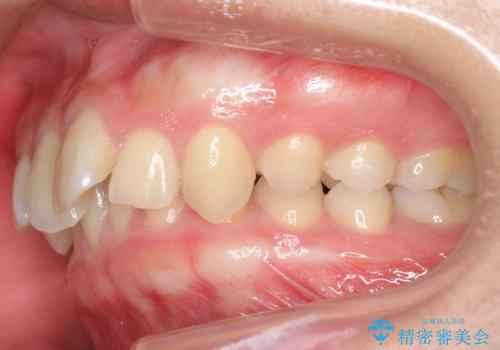

- 前歯の前突を主訴に来院。

かみ合わせが深く、また奥歯のかみ合わせも全体的に上が前にずれていました。

インビザライン矯正だけでなく、途中ワイヤー矯正もはさみました。前歯のかみ合わせが深く、本当に大変な治療でしたが協力度も高く非抜歯で上の奥歯を後ろに動かすことができました。